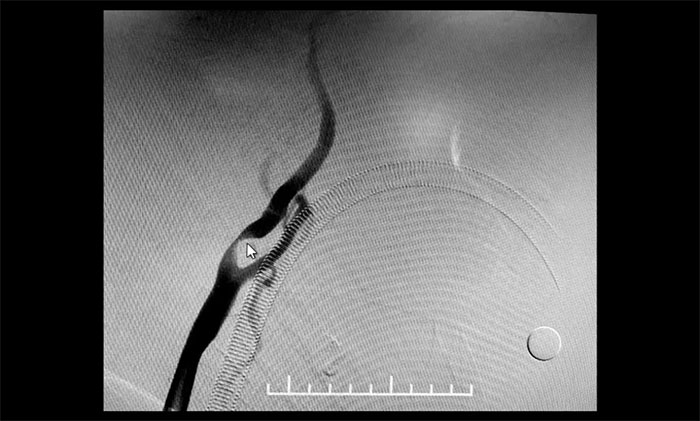

頸內(nèi)動(dòng)脈狹窄可分為輕度(<50%),中度(50%~69%)和重度(70%~99%),椎動(dòng)脈狹窄的判別標(biāo)準(zhǔn)與之相仿。DSA檢查示:患者雙側(cè)頸內(nèi)動(dòng)脈及左側(cè)椎動(dòng)脈存在重度狹窄,狹窄程度達(dá)到甚至超過(guò)90%,病情十分嚴(yán)重,遂立即收治入院。

▲ 雙側(cè)頸內(nèi)動(dòng)脈及左側(cè)椎動(dòng)脈重度狹窄